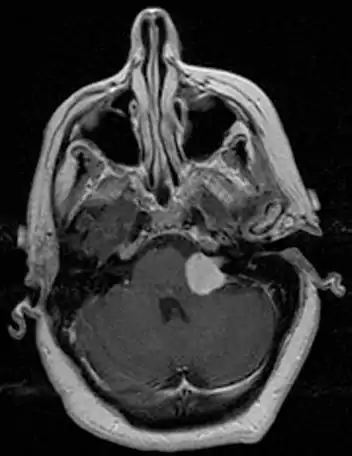

There have been cases of tumors that were actually asymptomatic until very large and at a critical stage. Tumor growth rates are highly variable: some small VSs (perhaps 50%) do not grow at all; some few grow for a time and then shrink; some appear dormant but suddenly grow rapidly. In general, although studies differ, VSs that grow are slow-growing at an average rate of 1.2 to 1.9 mm per year. IAC tumors that grow beyond 1.5 cm in diameter expand into the relatively empty space of the cerebellopontine angle, taking on the characteristic 'ice-cream-cone' appearance seen on MRIs. As 'space-occupying-lesions,' the tumors can reach 3 to 4 cm or more in size and infringe on the facial nerve (facial expression) and trigeminal nerve (facial sensation). Advanced hearing loss and spells of true vertigo may occur. Very large tumors are life-threatening when they press on the cerebellum or cause brainstem compression. Late symptoms of very large VS include headache, nausea, vomiting, sleepiness, mental confusion and eventually coma.[3][4]

MRI scan is the imaging of choice because it can more accurately differentiate the mass from other tumors such as meningioma, facial nerve schwannoma, epidermoid cyst, arachnoid cyst, aneurysm, and brain metastasis. MRI scan also helps in surgical planning and follow-up of the tumor after surgery.[19] VC is usually isointense on T1 weighted images, hyperintense on T2 weighted images, and enhances after given gadolinium contrast.[20] The use of MRI however should be used appropriately as patients with unilateral tinnitus alone